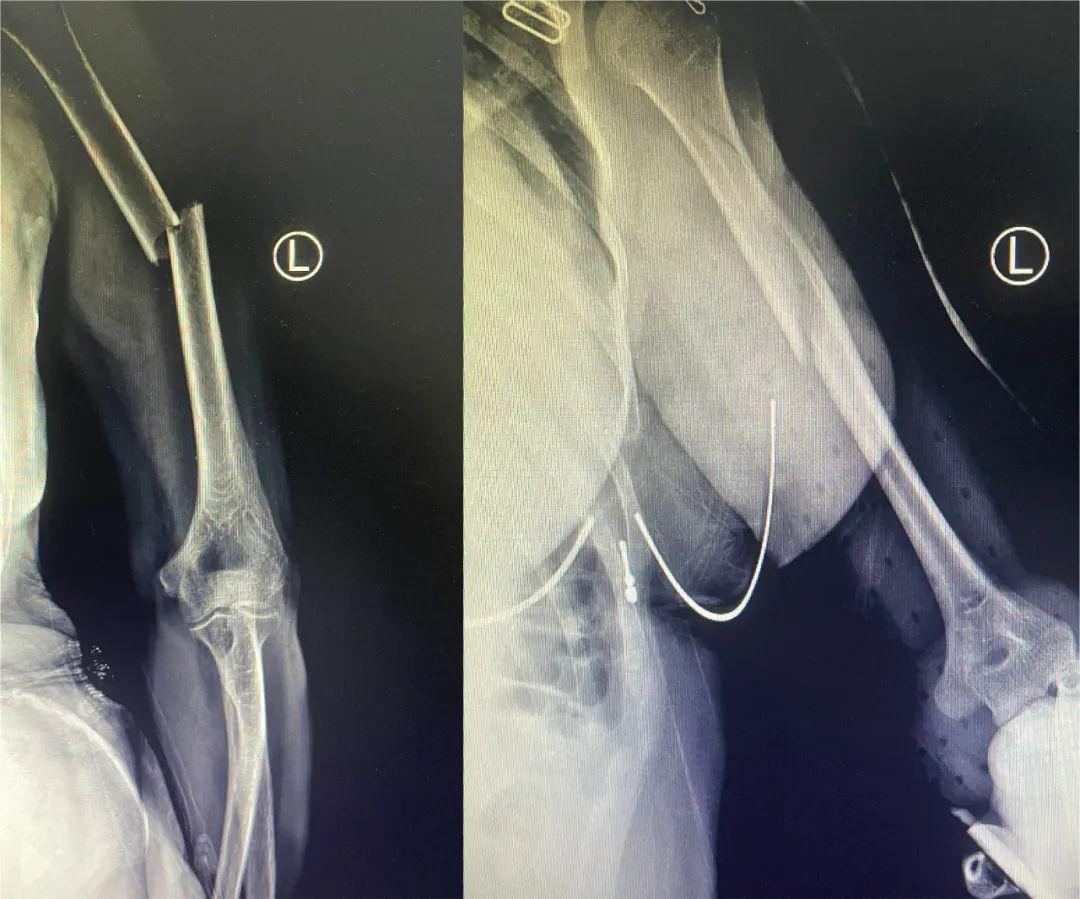

髓内钉固定

图片